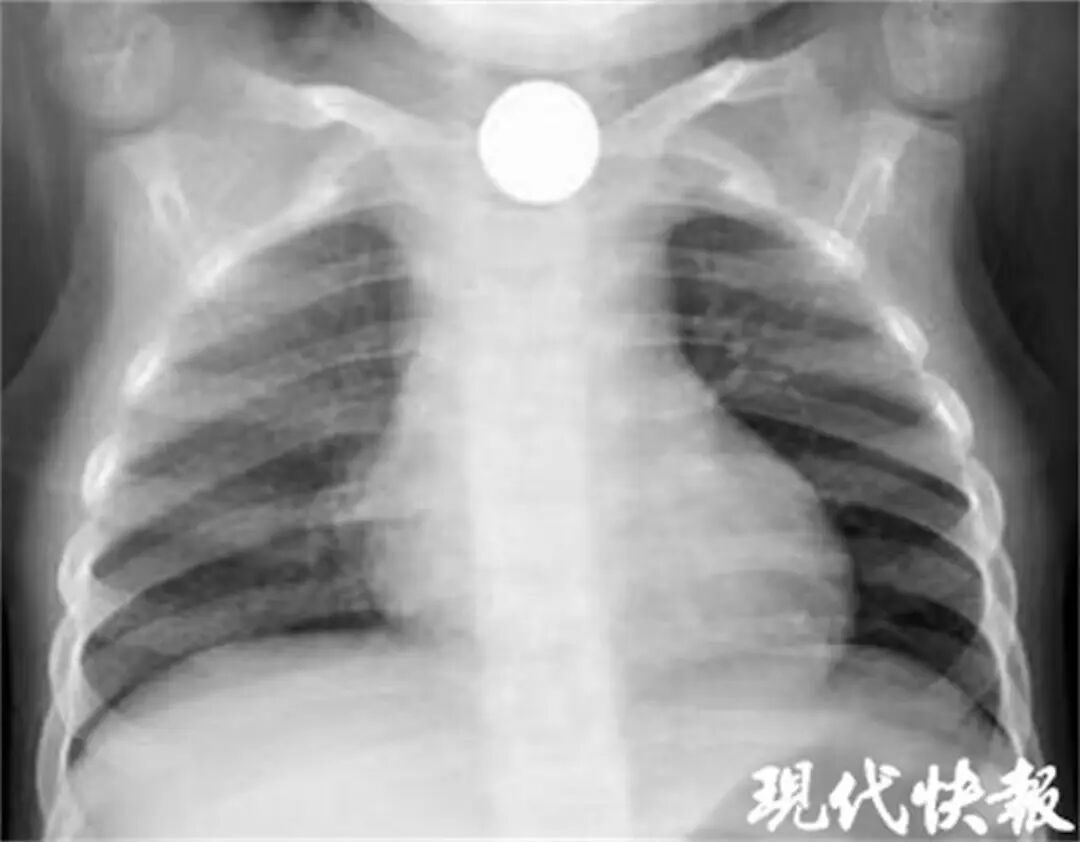

医生原以为是肺部疾病,但X光片显示患儿颈胸部有一个圆形金属阴影。医生判断,气喘可能与异物误入食道有关。

X光片显示患儿颈胸部有一个圆形金属阴影。(现代快报)